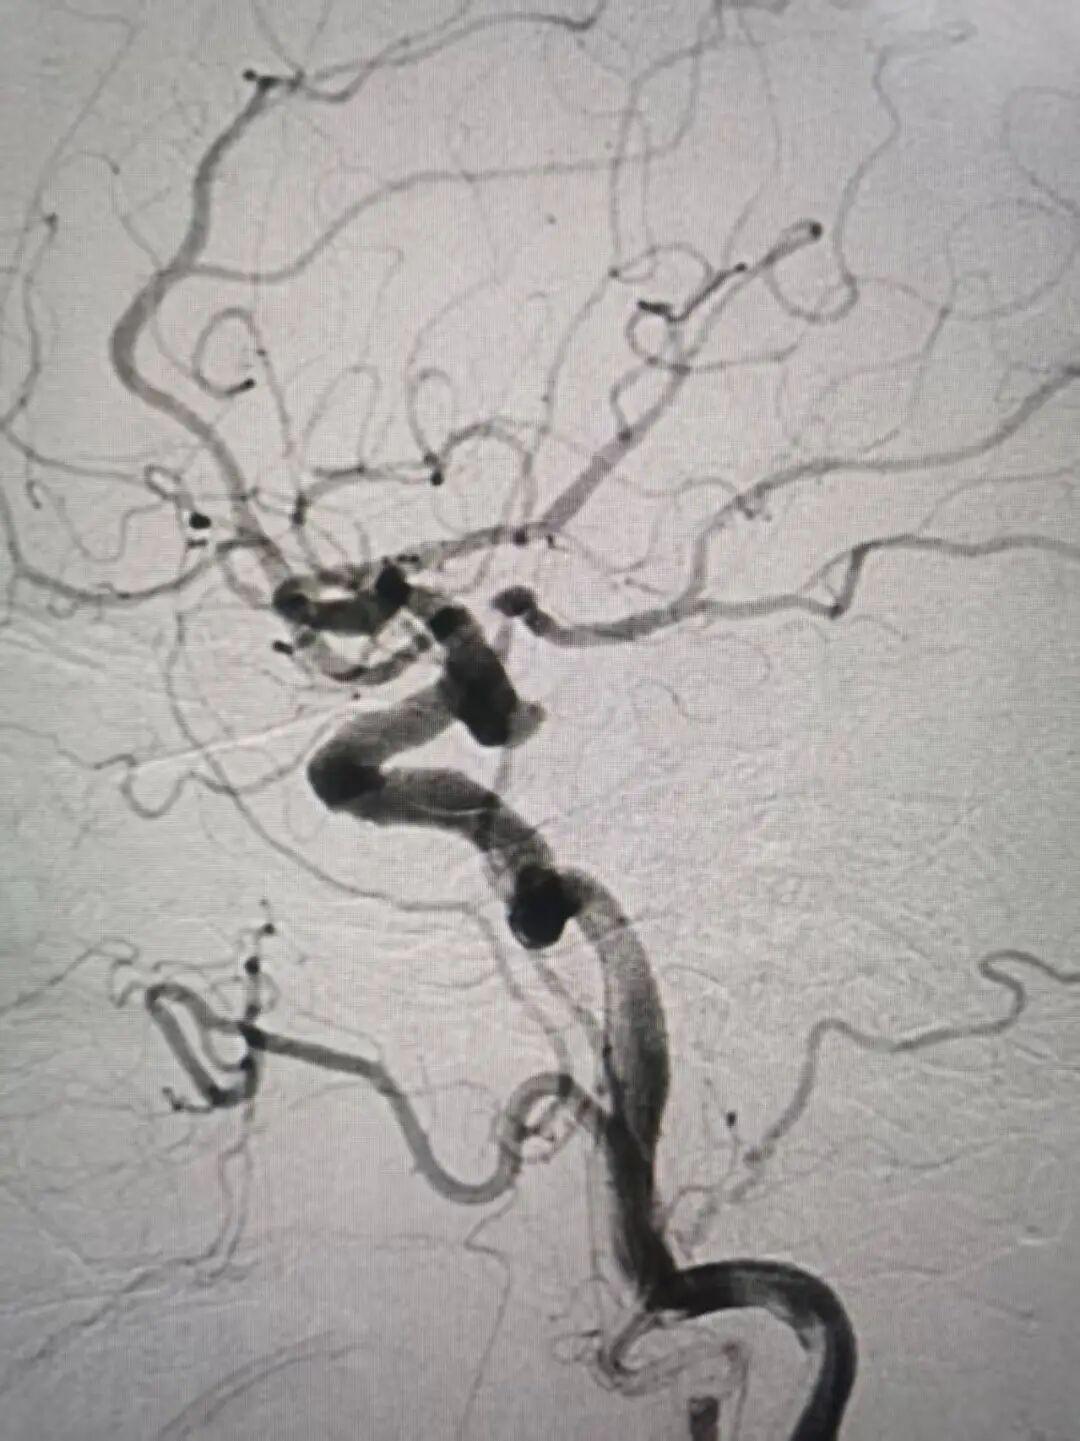

手术在全身麻醉下进行。然而,术中脑血管造影揭示了一系列严峻的解剖挑战:患者为罕见的“三型主动脉弓”,且腹主动脉严重迂曲,这如同血管路径上设置了多重“急弯”,使得导管导丝超选到位异常困难。更复杂的是患者的左侧大脑后动脉为“胚胎型”,且这根至关重要的血管恰恰从动脉瘤体上直接发出,这意味着在栓塞动脉瘤的同时,必须绝对保证这条大脑后动脉的通畅,否则将导致严重后果,手术难度与风险陡然倍增。

此次手术核心难关在于如何既能完美栓塞动脉瘤,又能保护紧邻的命脉血管。手术团队果断决策,采用“支架辅助栓塞”方案。在精确释放一枚颅内支架跨越动脉瘤颈后,主刀医生运用了业内高难度的“神龙摆尾”技术,对支架进行精细调整与释放。该技术犹如为微导丝、微导管赋予了灵性,使其能在毫米级别的血管空间内精准“摆尾”定位,从而确保支架完美覆盖瘤颈,同时为大脑后动脉留出畅通无阻的血流通道。

通道建立,保护到位。随后,一枚枚柔软的弹簧圈被精准填入动脉瘤腔内,致密填塞,彻底消除了破裂风险。最终造影显示:动脉瘤被完全栓塞,不再显影;而左侧大脑后动脉血流通畅,无任何狭窄或闭塞,手术取得圆满成功!